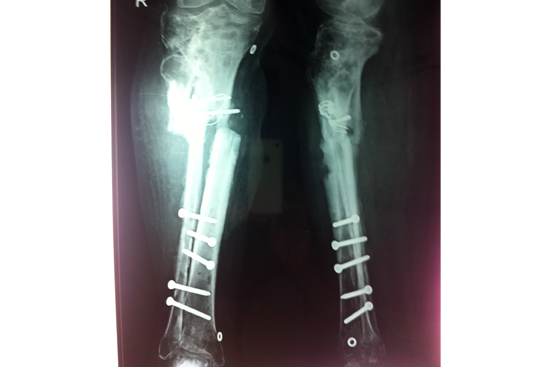

Tibialisation Of Fibula

Shankar Giri

Sudama

Wagh